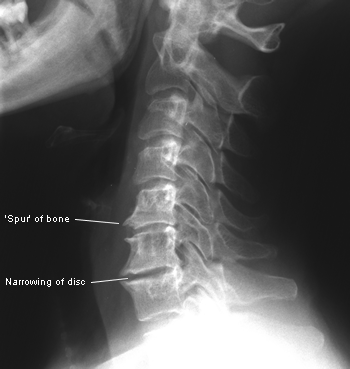

In the spine there are two curves called lordosis. These curves help the spine absorb and redirect forces. (to which it is constantly exposed) The second line of defense is the discs that are between each vertebrae. Each disk is like a fat rubber washer that separates, cushions and protects the bone and joints. Each bone, to stay healthy, must be able to move fully in 6 planes of motion (flexion-extension, rotation left and right, and lateral bending left and right) With proper motion the disk absorbs water and hydrates itself so it can stay fat and spongy and do it's work. Loss of this range of motion dehydrates the disk making it thinner decreasing the size of the hole (intervertebral foramen) thru which the nerve roots pass. Nerve compression then occurs.

Long term degeneration can cause "Stenosis" which is a narrowing of the canal thru which the nerve roots pass or even of the spinal cord itself, because bone spurs begin to occupy the space. With enough time the disks wear out so much that they are too thin to protect and the bone spurs grow out so much they interlace and fuse the vertebrae. The result is that you suffer a great deal and lose function gradually which limits you and decreases the quality of your life. The good news is that Chiropractic can help.